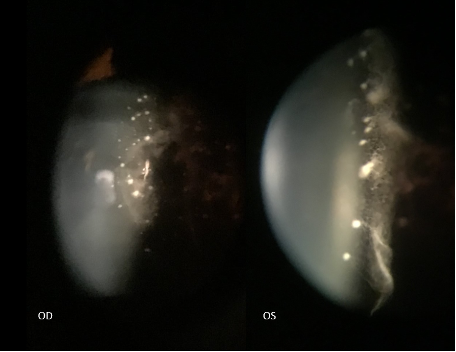

Slit lamp photography of both eyes showing the posterior lenticular deposits with glass wool-like vitreous opacities in the anterior vitreous.